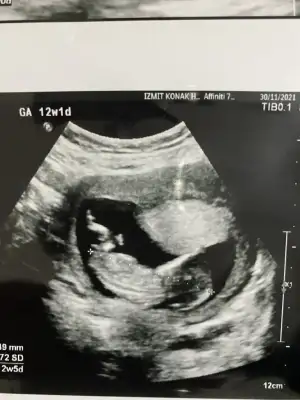

Merhabalar acaba buna bakabilir misiniz 13 haftalık karından

Eklentiler

• 2B80F9FF-B125-43D7-8AE8-07EFF3E3A46B.webp

2B80F9FF-B125-43D7-8AE8-07EFF3E3A46B.webp

59,6 KB · Görüntüleme: 61